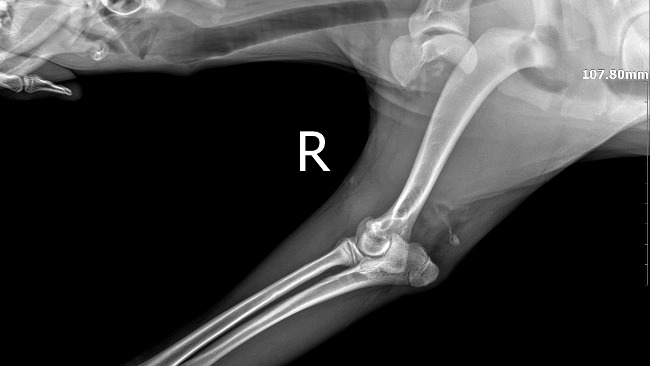

Harry to młodziutki (ok.1 roku) wyżełek po wypadku komunikacyjnym, w którym ucierpiały jego łapki. Łapka przednia wymaga natychmiastowej interwencji chirurgicznej!!!

Dołączam zdjęcia rtg łapek, które ucierpiały oraz opis z lecznicy.